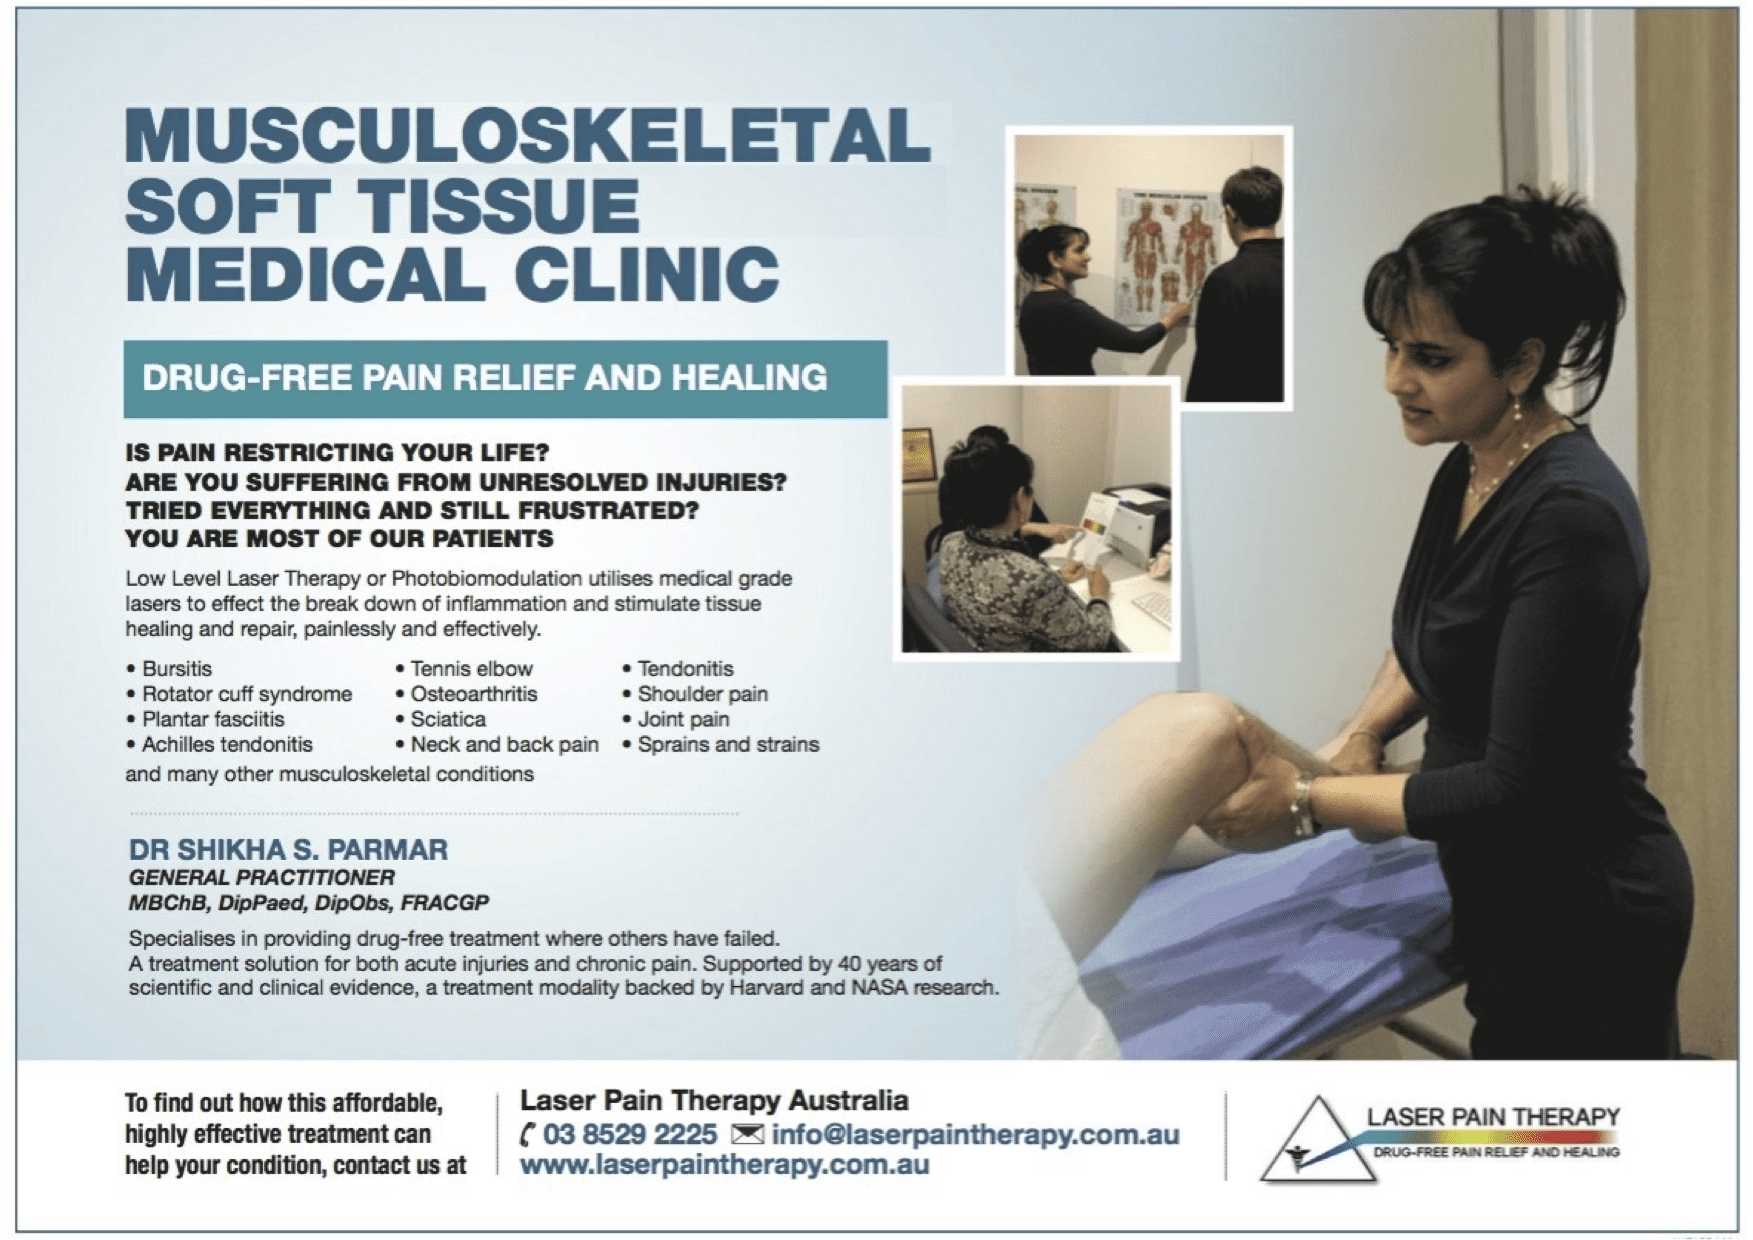

Low Level Laser Therapy (LLLT), also known as Photobiomodulation Therapy (PBMT), is a highly effective, non-invasive, and drug-free treatment for various ankle heel and foot soft tissue injuries. Led by Dr Shikha Parmar, a GP with expertise in managing and resolving chronic musculoskeletal pain utilising LLLT as part of a holistic management plan. LLLT involves the application of red and near-infrared light to promote cellular repair in injured tissues. LLLT is safe and painless, and targets the root cause of the injury, unlike pain medications that simply mask the symptoms. Supported by scientific research from respected institutions such as Harvard University and NASA, LLLT is an evidence-based therapy for soft tissue injuries, including tendon and ligament injuries, bursitis, plantar fasciitis, nerve injury, osteoarthrits and stress fractures.

GP, Dr Shikha Parmar, has a special interest in providing a drug-free safe, effective treatment solution in Melbourne for acute injuries and chronic pain using Low Level Laser Light therapy also termed Photobiomodulation or PBM Therapy.